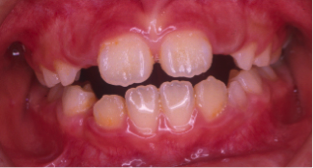

開咬(かいこう)

24歳/女性

悩み:前歯が噛めない

奥歯は噛み合っていても上と下の歯に隙間が空いてしまう状態

治療期間:約3年

治療前

治療後

前歯で噛む事が出来ないとの悩みから来院された患者様で、開咬症例ではあるのですが突出傾向があったため、小臼歯4本抜歯をする治療方針で約三年ほどかかって治療いたしました。治療後にはきちんとものが噛めるようになり、約三年間の頑張りが報われましたと喜んで頂けました。